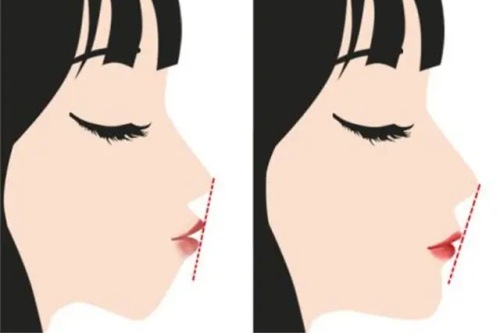

特别值得一提的是,该院创新的"3D动态轮廓设计"技术,不仅考虑静态面部比例,更在意表情时的自然动态结果。

术前她的面部线条较为硬朗,颧骨突出明显。

术后6个月随访显示,面部轮廓变得柔和流畅,但保留了个人特色,没有出现千篇一律的"网红脸"结果。

小创口截骨技术:采用特殊器械缩小截骨面积,减少组织损伤

立体缝合技术:多层精细缝合确保皮肤贴合骨骼新轮廓